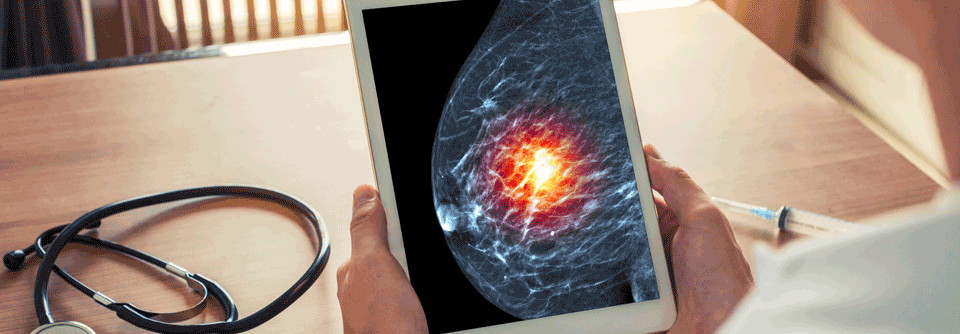

Am 20. September 2022 fand zudem ein 45-minütiges Live-Webinar statt. Unsere Referentin, Frau Prof. Dr. Diana Lüftner, Immanuel Klinik Märkische Schweiz, Buckow, hat ihre Kongresshighlights zum Thema Brustkrebs zusammengefasst und Fragen aus dem Publikum beantwortet. Im Vortrag hat sie die drei Themenblöcke endokrine Therapie, Antikörper-Wirkstoff-Konjugate und Immuntherapie aufgegriffen. Das Webinar steht zeitnah als On-demand-Version zur Verfügung und soll mit zwei CME-Punkten zertifiziert werden. Die Zertifizierung ist für ein Jahr geplant.

Brustkrebs-Highlights | Prof. Dr. med. Diana Lüftner | ESMO 2022

Mammakarzinom

„Provokante“ Ergebnisse

Mit dem Lokalanästhetikum Lidocain lässt sich einer Studie aus Indien zufolge das Gesamtüberleben von Erkrankten mit frühem Mammakarzinom signifikant…

Brustkrebs

Sacituzumab Govitecan mit OS-Vorteil bei HR+/HER2- metastasiertem Brustkrebs

In der TROPiCS-02-Studie wird Sacituzumab Govitecan bei intensiv vorbehandelten Personen mit HR+/HER2- metastasiertem Mammakarzinom geprüft.…

Frauen mit frühem HR+/HER2- Mammakarzinom profitieren

Erste Daten aus der ADAPTcycle-Studie, die mit denen aus ADAPT abgeglichen wurden, bestätigen die kurze präoperative endokrine Therapie als wichtiges…

MONARCH 3: Zweite geplante Interimsanalyse zeigt klare Wirksamkeitsvorteile

Die zweite geplante Zwischenanalyse der MONARCH3-Studie bei postmenopausalen Patient:innen mit HR+/HER2- fortgeschrittenem Mammakarzinom zeigt einen…